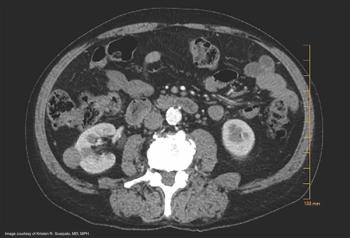

An expert panel discusses the case of a 65-year-old Caucasian male who is noted to have an incidental 3-cm right renal mass, enhancing on a contrasted CT scan as part of a routine follow-up for his metastatic castration-resistant prostate cancer, diagnosed in 2017 and currently undergoing therapy.

Determining grade of disease is important, as nephron-sparing approaches may be feasible.

Renal mass biopsy should be used for patients in whom results would impact management decisions.